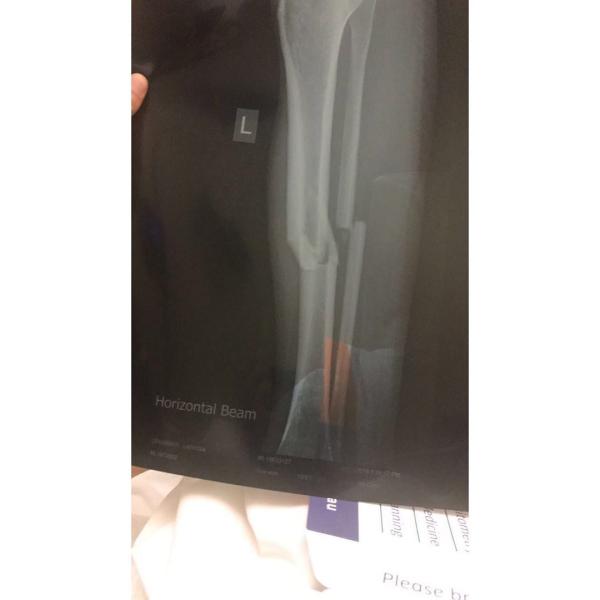

Devastatingly for Crummer, in that moment, everything was not okay.  The collision had resulted in breaks in the tibia and fibula bones in her left leg.

Crummer Broken Leg

X-ray of the breaks in Crummer's left leg